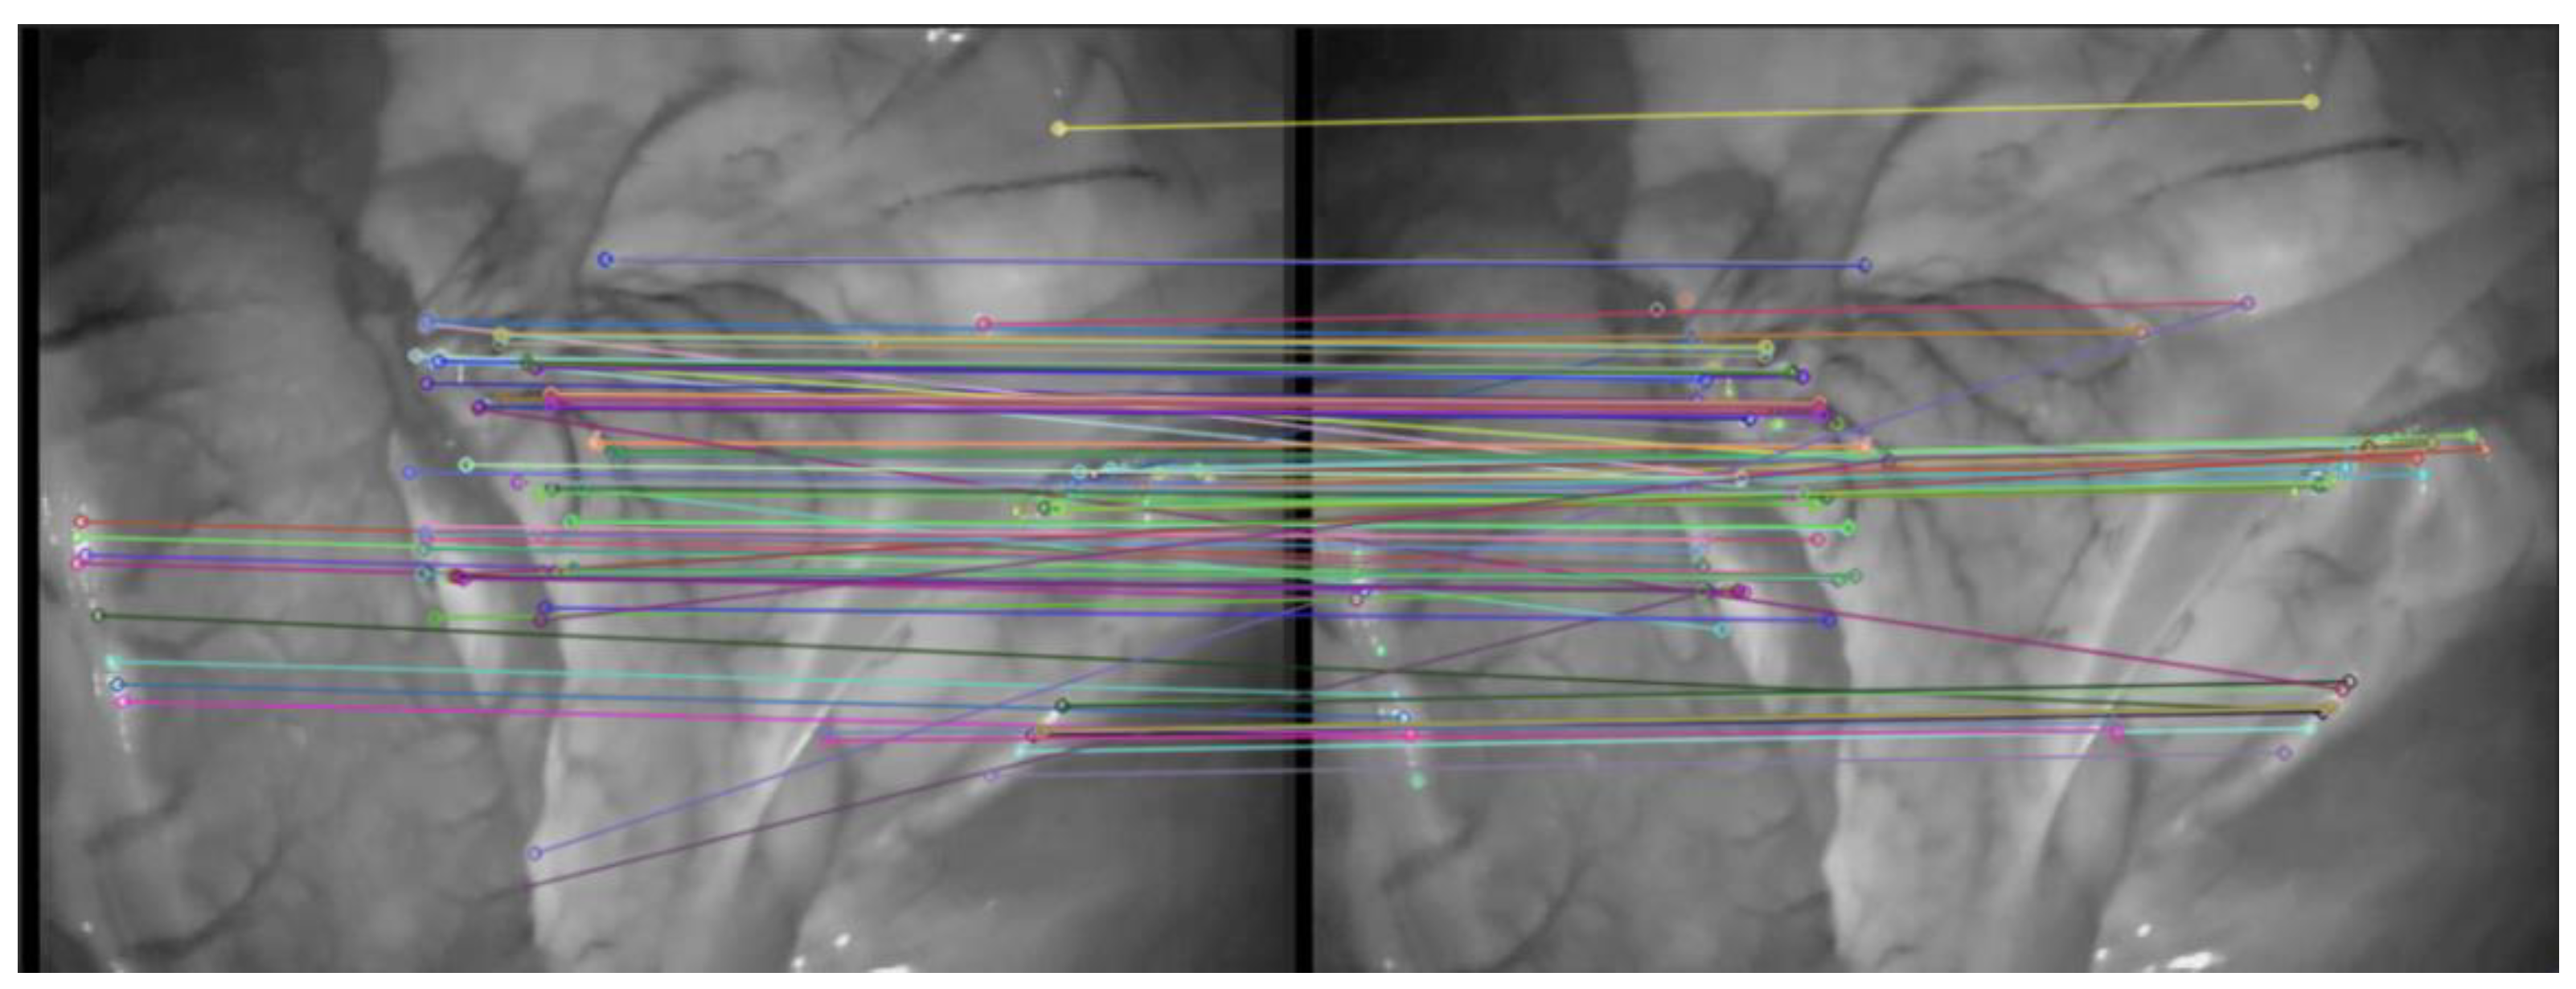

The effect of traditional ORB algorithm and AKAZE-ORB algorithm on extracting feature points of abdominal image frame is shown in Figure 4. The effect of AKAZE-ORB algorithm on abdominal image frame feature point matching is shown in Figure 5.

In order to improve the accuracy of feature matching, this paper uses the symmetry of feature points to quickly eliminate the majority of mis-matched pairs combined with the RANSAC algorithm, as shown in Figure 6.

Figure 5. Feature points matching results obtained by AKAZE-ORB.

Symmetry 14 00185 g005

Figure 6. The results of RANSAC algorithm to identify incorrect matches.

Symmetry 14 00185 g006